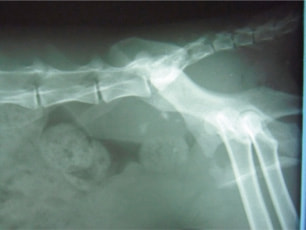

症例:交通事故による椎体脱臼

柴犬:9歳、避妊雌

交通事故直後、胸腰部に激しい疼痛、両後肢に完全麻痺を認め、シェフシェリントン徴候を呈していました。レントゲン検査において、第11-12胸椎間の脱臼が認められました。

脊髄の減圧、脊柱管の再構築・安定化を目的に、片側椎弓切除術およびMatrixMANDIBLE Plateによる椎体固定を実施しました。

隣接椎体を架橋するようにプレートを設置しました。

術後レントゲン写真